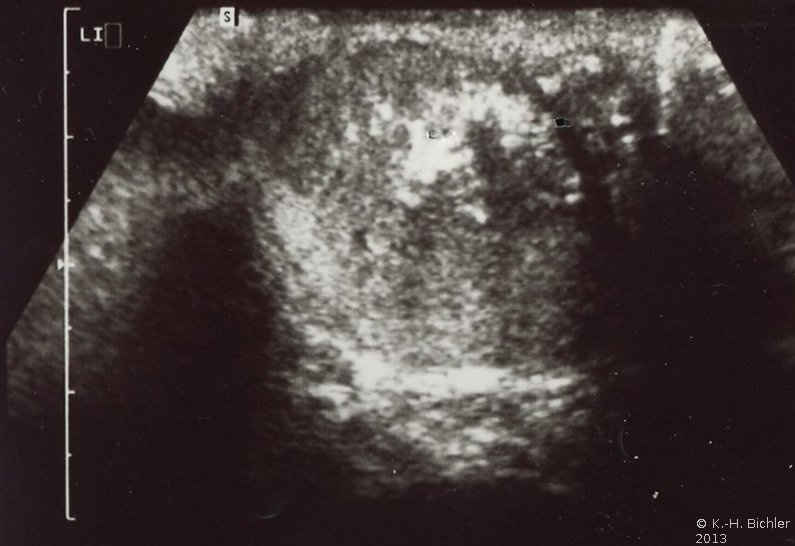

Bei dem jungen Mann fand sich bei der Vorstellung ein schmerzloser Hodentumor links. Die Sonographie ergab ein tumorverdächtiges Areal im linken Hoden mit deutlichem Schlagschatten (Abbildung 3).

In der histologischen Untersuchung fand sich intratubuläres embryonales Karzinom-Gewebe (pT2) mit fokalen Nekrosen und Verkalkungen (s. Abbildung 3). Die Zellen mit reichlich Zytoplasma, großen vesikulären Kernen und prominten Nucleoli (Abbildung 5). Fernerhin waren Seminomanteile enthalten.